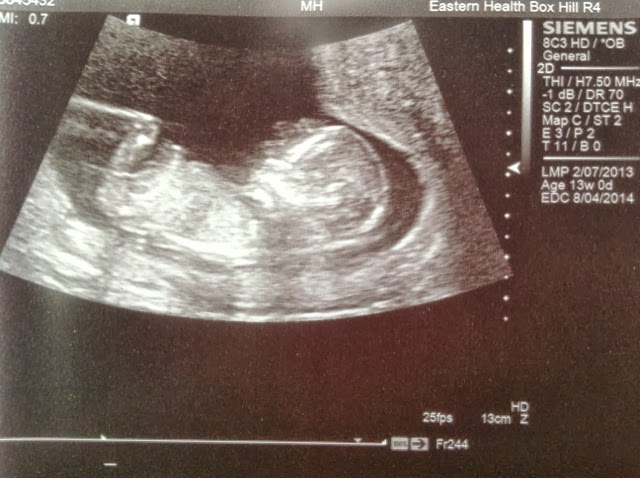

I know I've been slack with posting an update but I have just been really really tired.  At night I get home and just crash, so I haven't really had the energy to blog, but the scan which we ended up having at 13 weeks was fine.  Little one is doing everything it should which is great :).  Looking like a real little person now!  Due date based on growth came back as 05/04 but since this is slightly ahead of my original LMP based date (08/04) my mid wife suggested we stick with the 08/04 which is fine by me.  My first midwife appointment was last week and seemed pretty straight forward.  Lots of questions, gave me an pile of info booklets etc and talked about birthing and breast feeding classes they have at the hospital we will be delivering at.  We're keen to do the breast feeding class when we get closer to the due date but I'm not so sure about the birthing classes.  They're obviously going to be full of hetero couples and I'm just not sure it's something either of us are keen on putting ourselves through.  Scout never did birthing classes when she was pregnant with the girls and doesn't think it's necessary so I think we might skip it.  I don't know if anyone else has any thoughts on this?  Anyway ... Here's the pic from our scan.  They only gave me one and it's a bit fuzzy so we've decided to go somewhere else for the 20 week scan.

Scan was great :).  Much better than the 12 week one.  We went to a different place this time and it was so worth it!  Had a really nice guy doing it and we got to see baby in 4D which was awesome.  Little one was super active moving around the entire time so he had to do a fair bit of chasing but apparently everything looked pretty normal which is great :). Only thing he did mention was that the placenta is very low and close to the cervix so I have to go back for another scan around 34 weeks to see if it's moved up out of the way or not.  If it doesn't move then it's likely I'll have to have a c-section.  Fingers crossed that's not the case, but I'm not going to worry about it for now.  Alot of people have told me they had this and theirs moved so hopefully that will be the case with this one too :)  Anyway here's a pic of our little one!